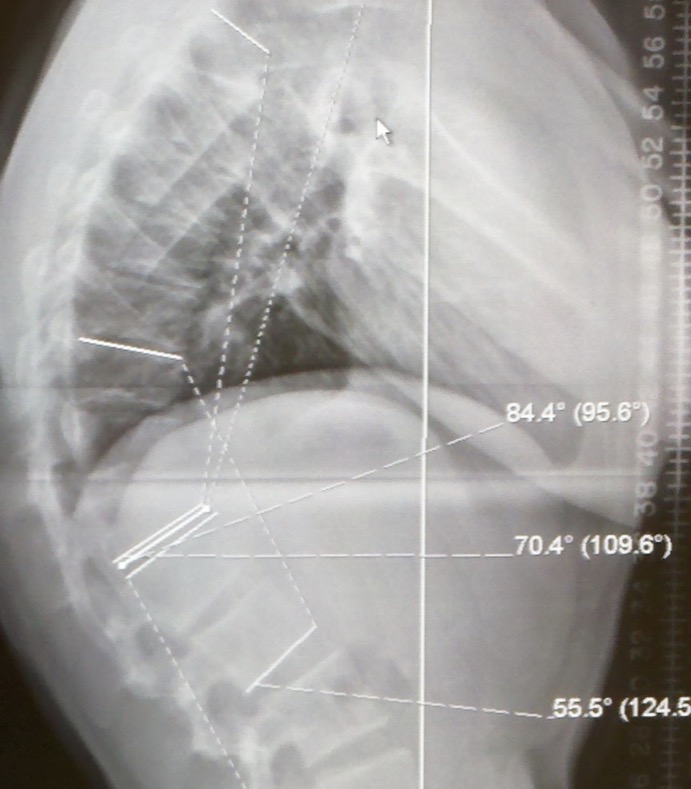

Rx Rachis Dorsal de profil debout

Colonne in toto F/P

1. Cyphose > 50°

4. Vertèbres cunéiformes >5° (déformation en coin du corps) au sommet de la cyphose > 3 vertèbres adjacentes

5. Plateaux irréguliers et feuilletés

6. Hernies intra-spongieuses ou rétro-marginales antérieures (Schmorl)

7. Possible tassement discal